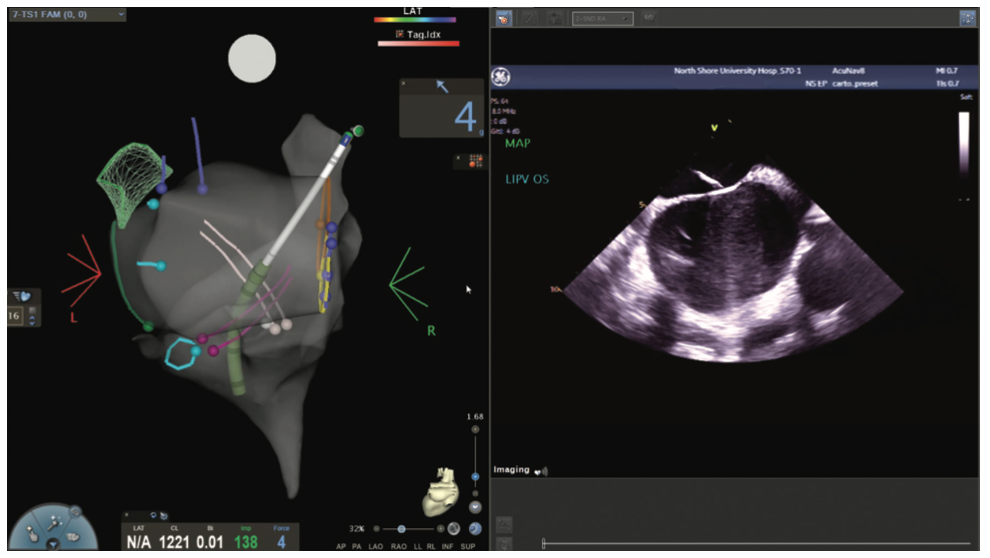

Figures/Videos 1-10 demonstrate the process of navigation from groin access to the heart to create biatrial geometry, localize the esophagus, and gain transseptal access. Many currently practicing electrophysiologists use very little fluoroscopy to map and ablate the left atrium (LA) with the current multielectrode catheters and EAM systems once transseptal access is obtained.

Video 15a and Figures 15b-d show ablation of premature ventricular contractions (PVCs) arising from the aortic coronary cusps, initially attempted from the posterior right ventricular outflow tract. The pace maps and very low amplitude fractionated electrograms from the ablation site are shown as well.